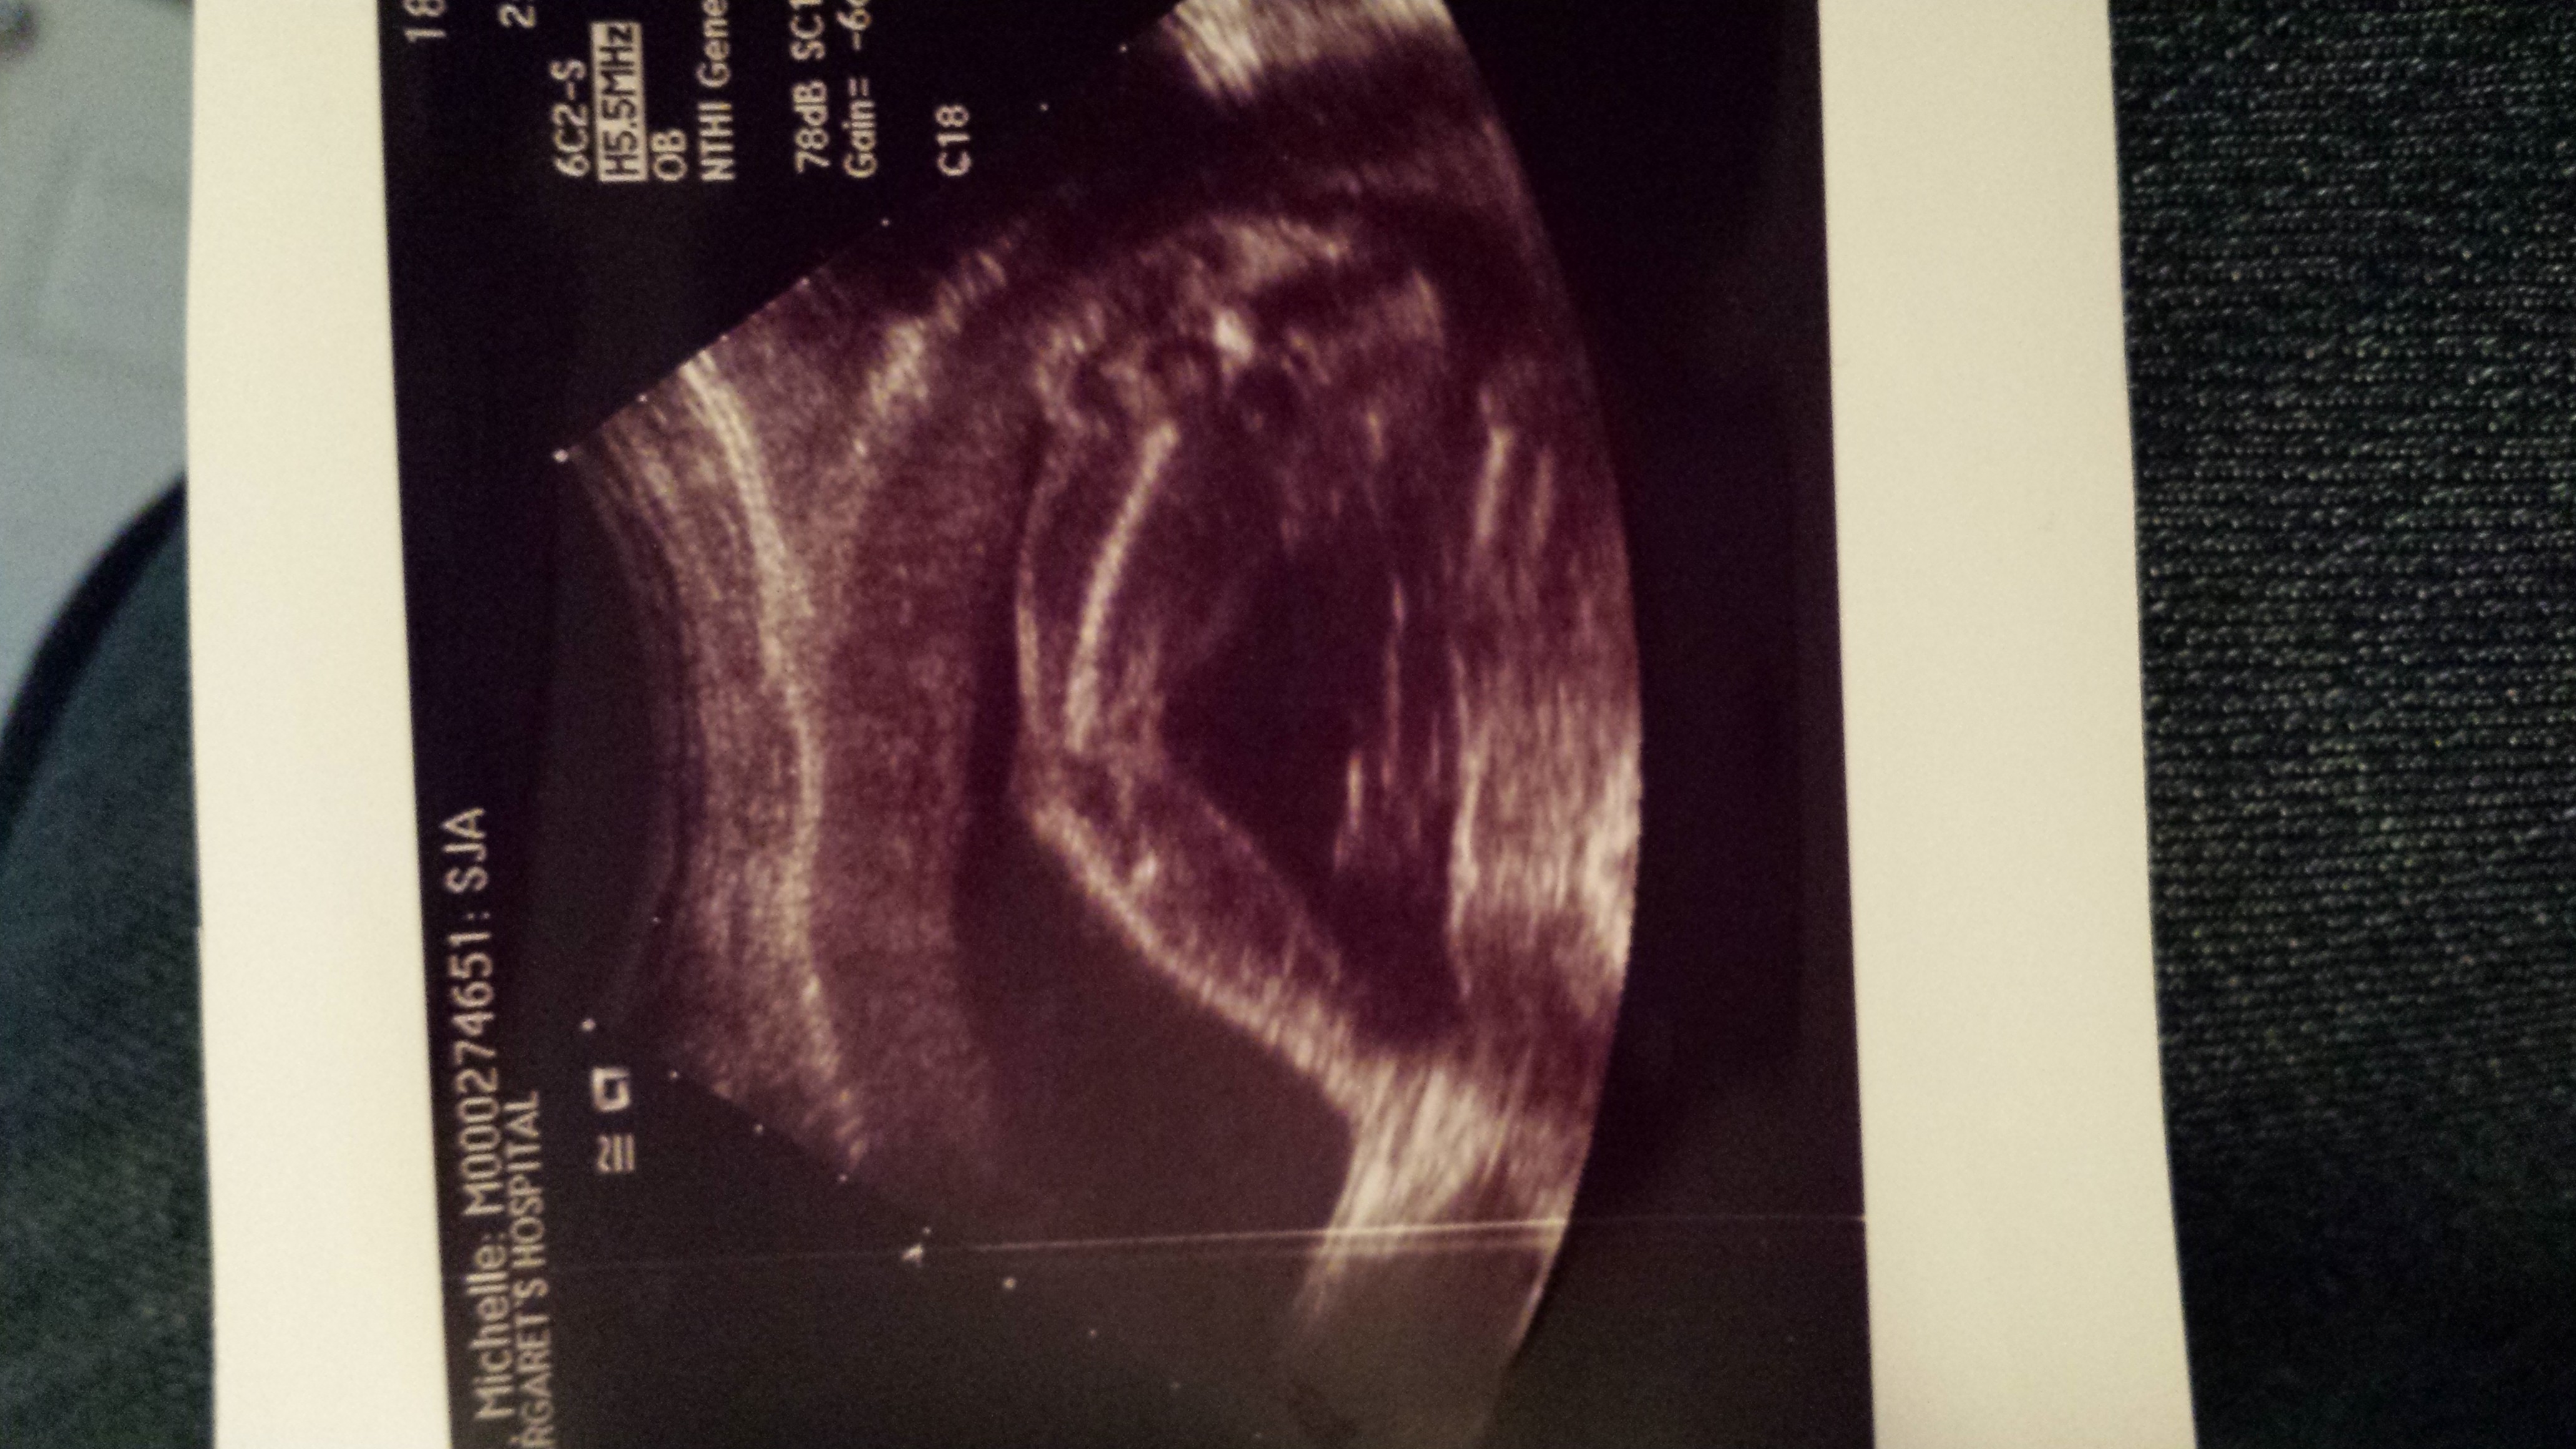

I'm 21w3d and I had my first ultrasound today. Due to a stubborn baby who wouldn't flip for a profile shot; unfortunately, I don't have a good picture other than a straight-on face pic.

I would really like to have an idea of the gender, but understand it's hard to tell without seeing profile.

Just for fun, what's your guess?Attachment 20460